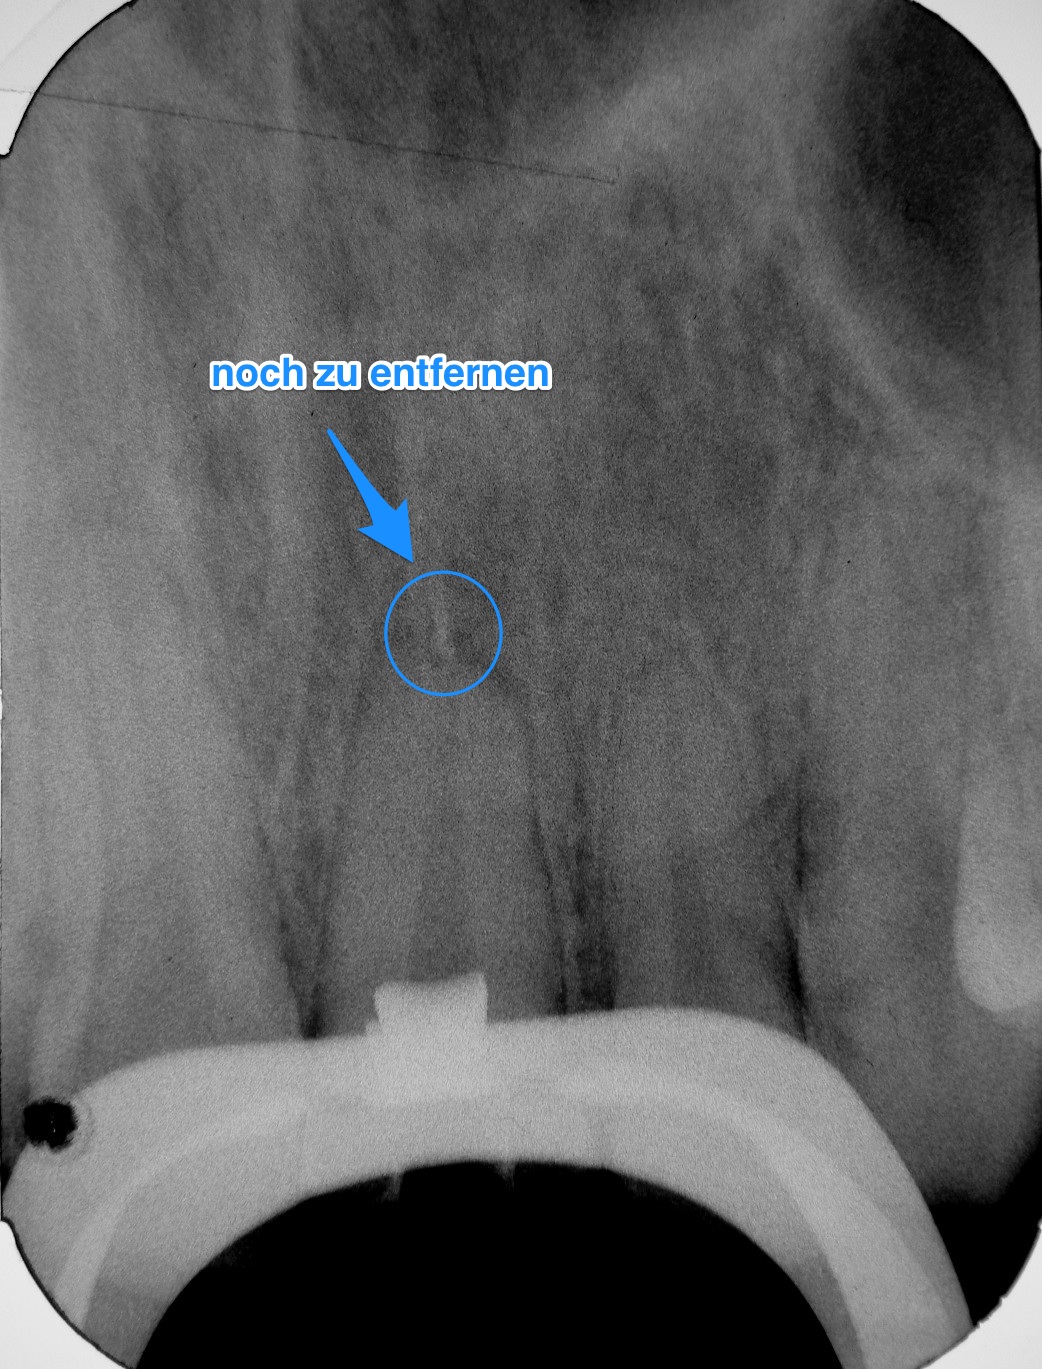

Hier und hier wurden die Angelhaken schon vorgestellt. Zum Einsatz kamen sie in diesem Fall, genauer gesagt hier. Die markierten Sealer/GP-Rest sollten noch entfern werden.

Es war letzt keine Sache von 10 Sekunden, aber die Angelhaken erleichterten die Entfernung der unerwünschten Überbleibsel sehr.

Blick durch den Apex, ohne GP-Reste

post Op, Reste entfernt

prae Op